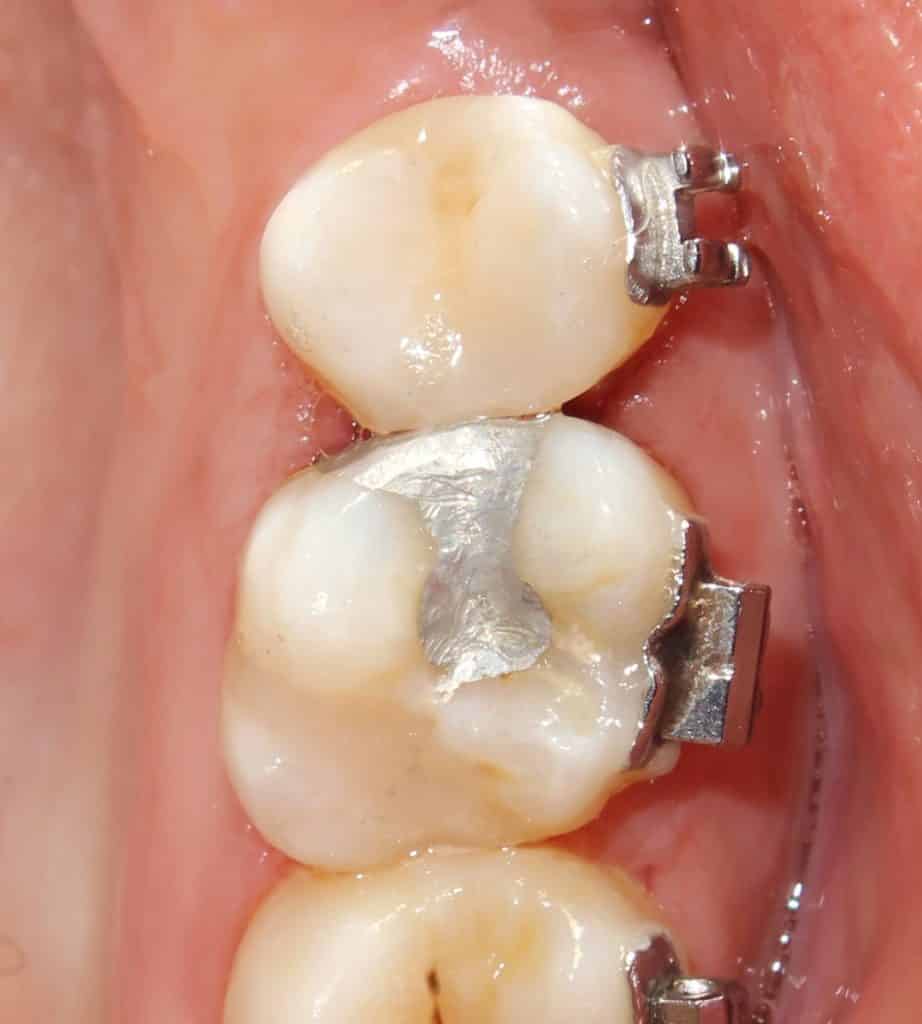

both preps are visualized.. the cervical margin of 15 is in enamel.. the margin of 16 is in dentin..

matrixing..

the completed work with amalgum done on 16 mesial.. and composites on all other cavities..